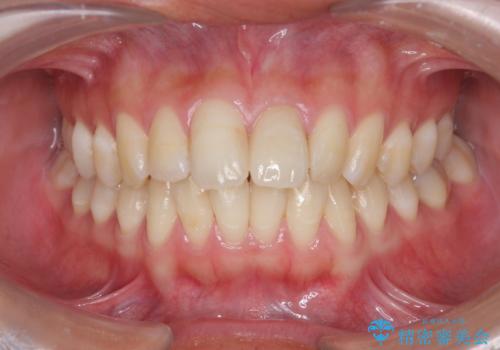

前歯の変色を改善するセラミッククラウン治療

- 以前に前歯を強打し、変色してきた前歯の審美性の改善を希望されて来院されました。

X線検査の結果、変色をきたしている歯は根尖病変が存在し、神経が失活している状態でした。

根管治療を行ったのち、セラミッククラウンで審美性を改善していきます。

歯科技工士との綿密な打ち合わせで、非常に自然なセラミッククラウンを作製することができました。